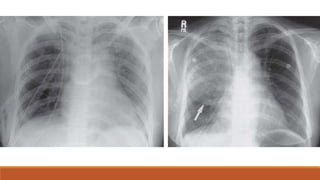

CT axial section contrast study shows displaced right rib fracture with extensive subcutaneous emphysema. There is also a

sternal fracture with associated retrosternal hematoma and lung window settings shows a large right pneumothorax.

CT scan demonstrates an anterior mediastinal hematoma with a preserved fat plane between the

hematoma and the aorta. Arrow indicates a sternal fracture.

CT axial sectioncontrast study shows displaced right rib fracture with extensive subcutaneous emphysema. There is also a sternal fracture with associated retrosternal hematoma and lung window settings shows a large right pneumothorax.

CT scan demonstratesan anterior mediastinal hematoma with a preserved fat plane between the hematoma and the aorta. Arrow indicates a sternal fracture.